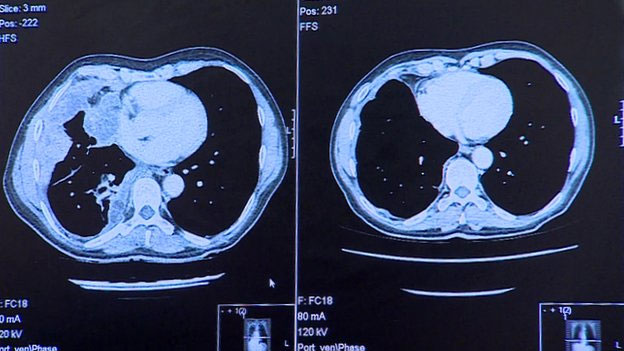

Exames em seu pulmões (como mostram as imagens acima) revelam que, depois de apenas três doses, o remédio parece ter removido completamente o câncer do órgão.